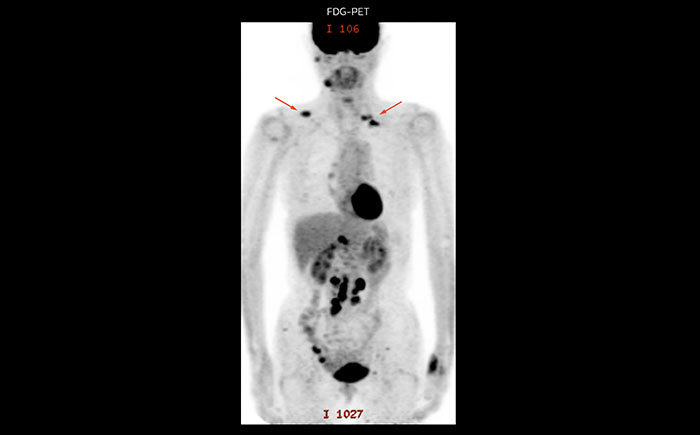

Whole body diffusion

A 61-year-old female with a malignant lymphoma underwent an MRI exam with whole body diffusion weighted imaging (DWIBS) as well as PET. On the images shown, the resolution of DWIBS is better than PET, which allows visualization of the small pelvic lesions and almost no distortion is seen in the neck area.

Prodiva MRI whole body DWI lymphoma, Seirei Mikatahara

Prodiva MRI whole body FDG-PET, Seirei Mikatahara